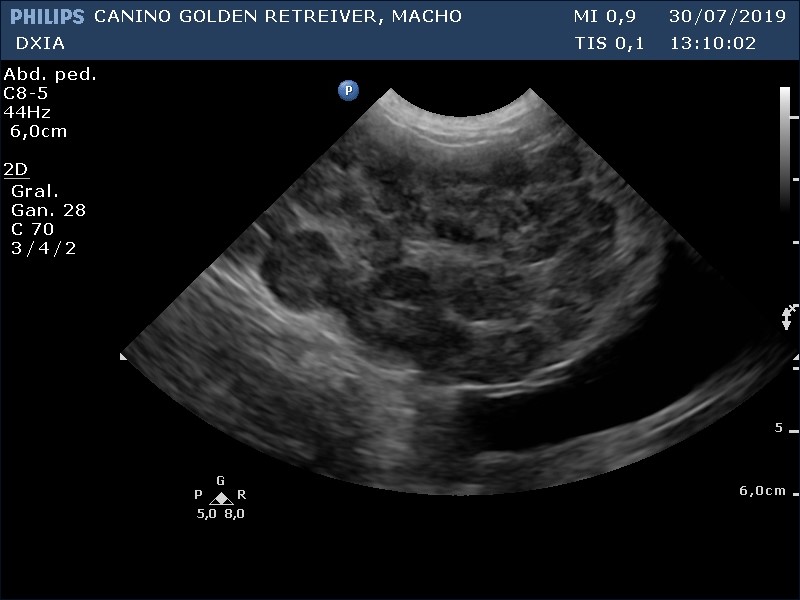

Corte apical craneal izquierdo optimizando cámaras derechas y VT. No se detecta la existencia de Filarias adultas cardíacas ni dilatación en cámaras derechas.